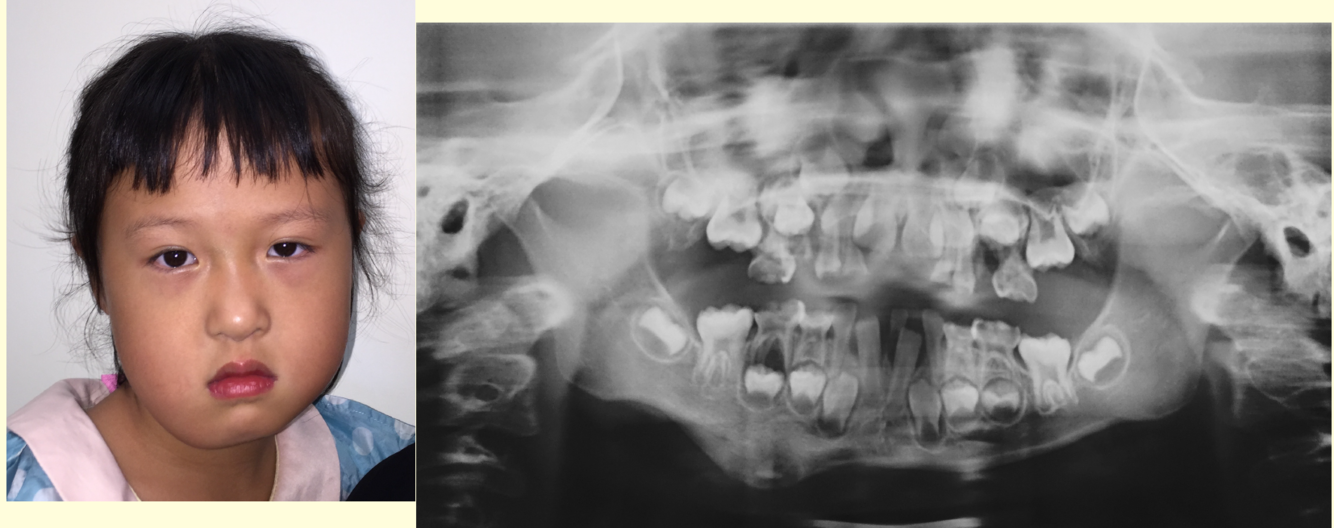

Q

What is this?

A

Fibrous dysplasia